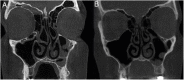

Objectives: The purpose of this study is to describe and assess the short- and long-term efficacy of a modified crushing technique for concha bullosa management.

Methods: Patients who met inclusion criteria underwent a detailed nasal examination and cone beam computed tomography imaging prior to and after septoplasty with crushing surgery for obstructive concha bullosa. Patients were divided into short- and long-term groups based on their followup period such that the short-term group had a mean followup of 15.14 months (range 6-22 months) and the long-term group had a mean followup of 56.66 (range 29-80) months.

Results: Twenty-four cases of obstructive concha bullosa were included in this study with 13 short-term and 11 long-term follow-ups. All patients showed a significantly decreased postoperative CB size (p < 0.001). There was no correlation between age and postoperative CB change in area (p = 0.39) and no significant difference in the amount of postoperative CB area reduction between the short-term and long-term groups (p = 0.35). No patients experienced bleeding, synechia, conchal destruction, or olfactory dysfunction on followup evaluations.

Conclusions: Our modified crushing technique is a simple, effective, and lasting treatment option for concha bullosa. From our experience, there have been no complications and no instances of concha bullosa reformation during the follow-up period.